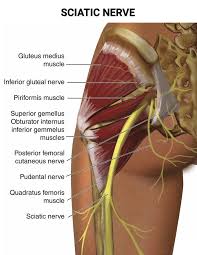

Download Sciatic nerve pain pictures